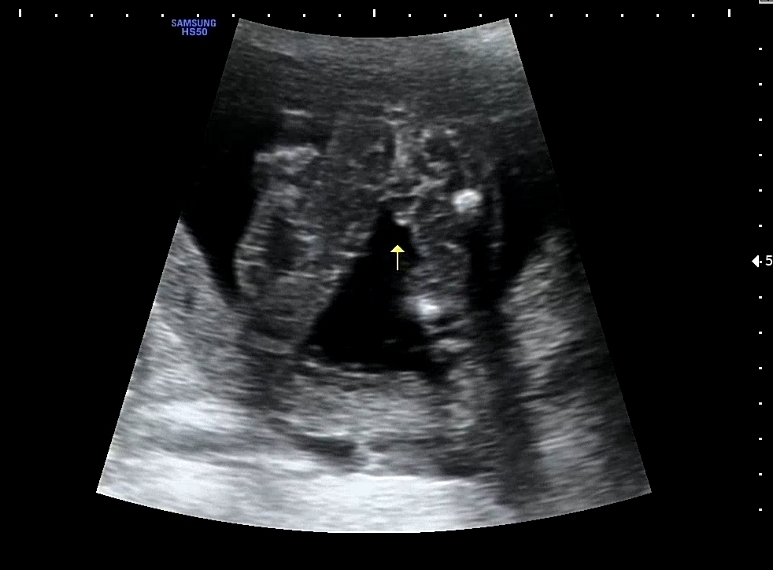

16주 0일 아들일까요 딸일까요?

의사선생님께서는 애매하시다는데 아들일까요 딸일까요?

ㅃ알 같습니다